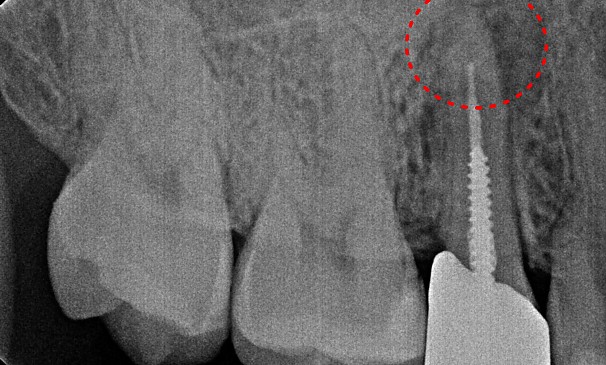

병든 뿌리 절제술

강OO님 전후사진 | 치료 기간 : 1주

치료 전

치료 후

병든뿌리절제술